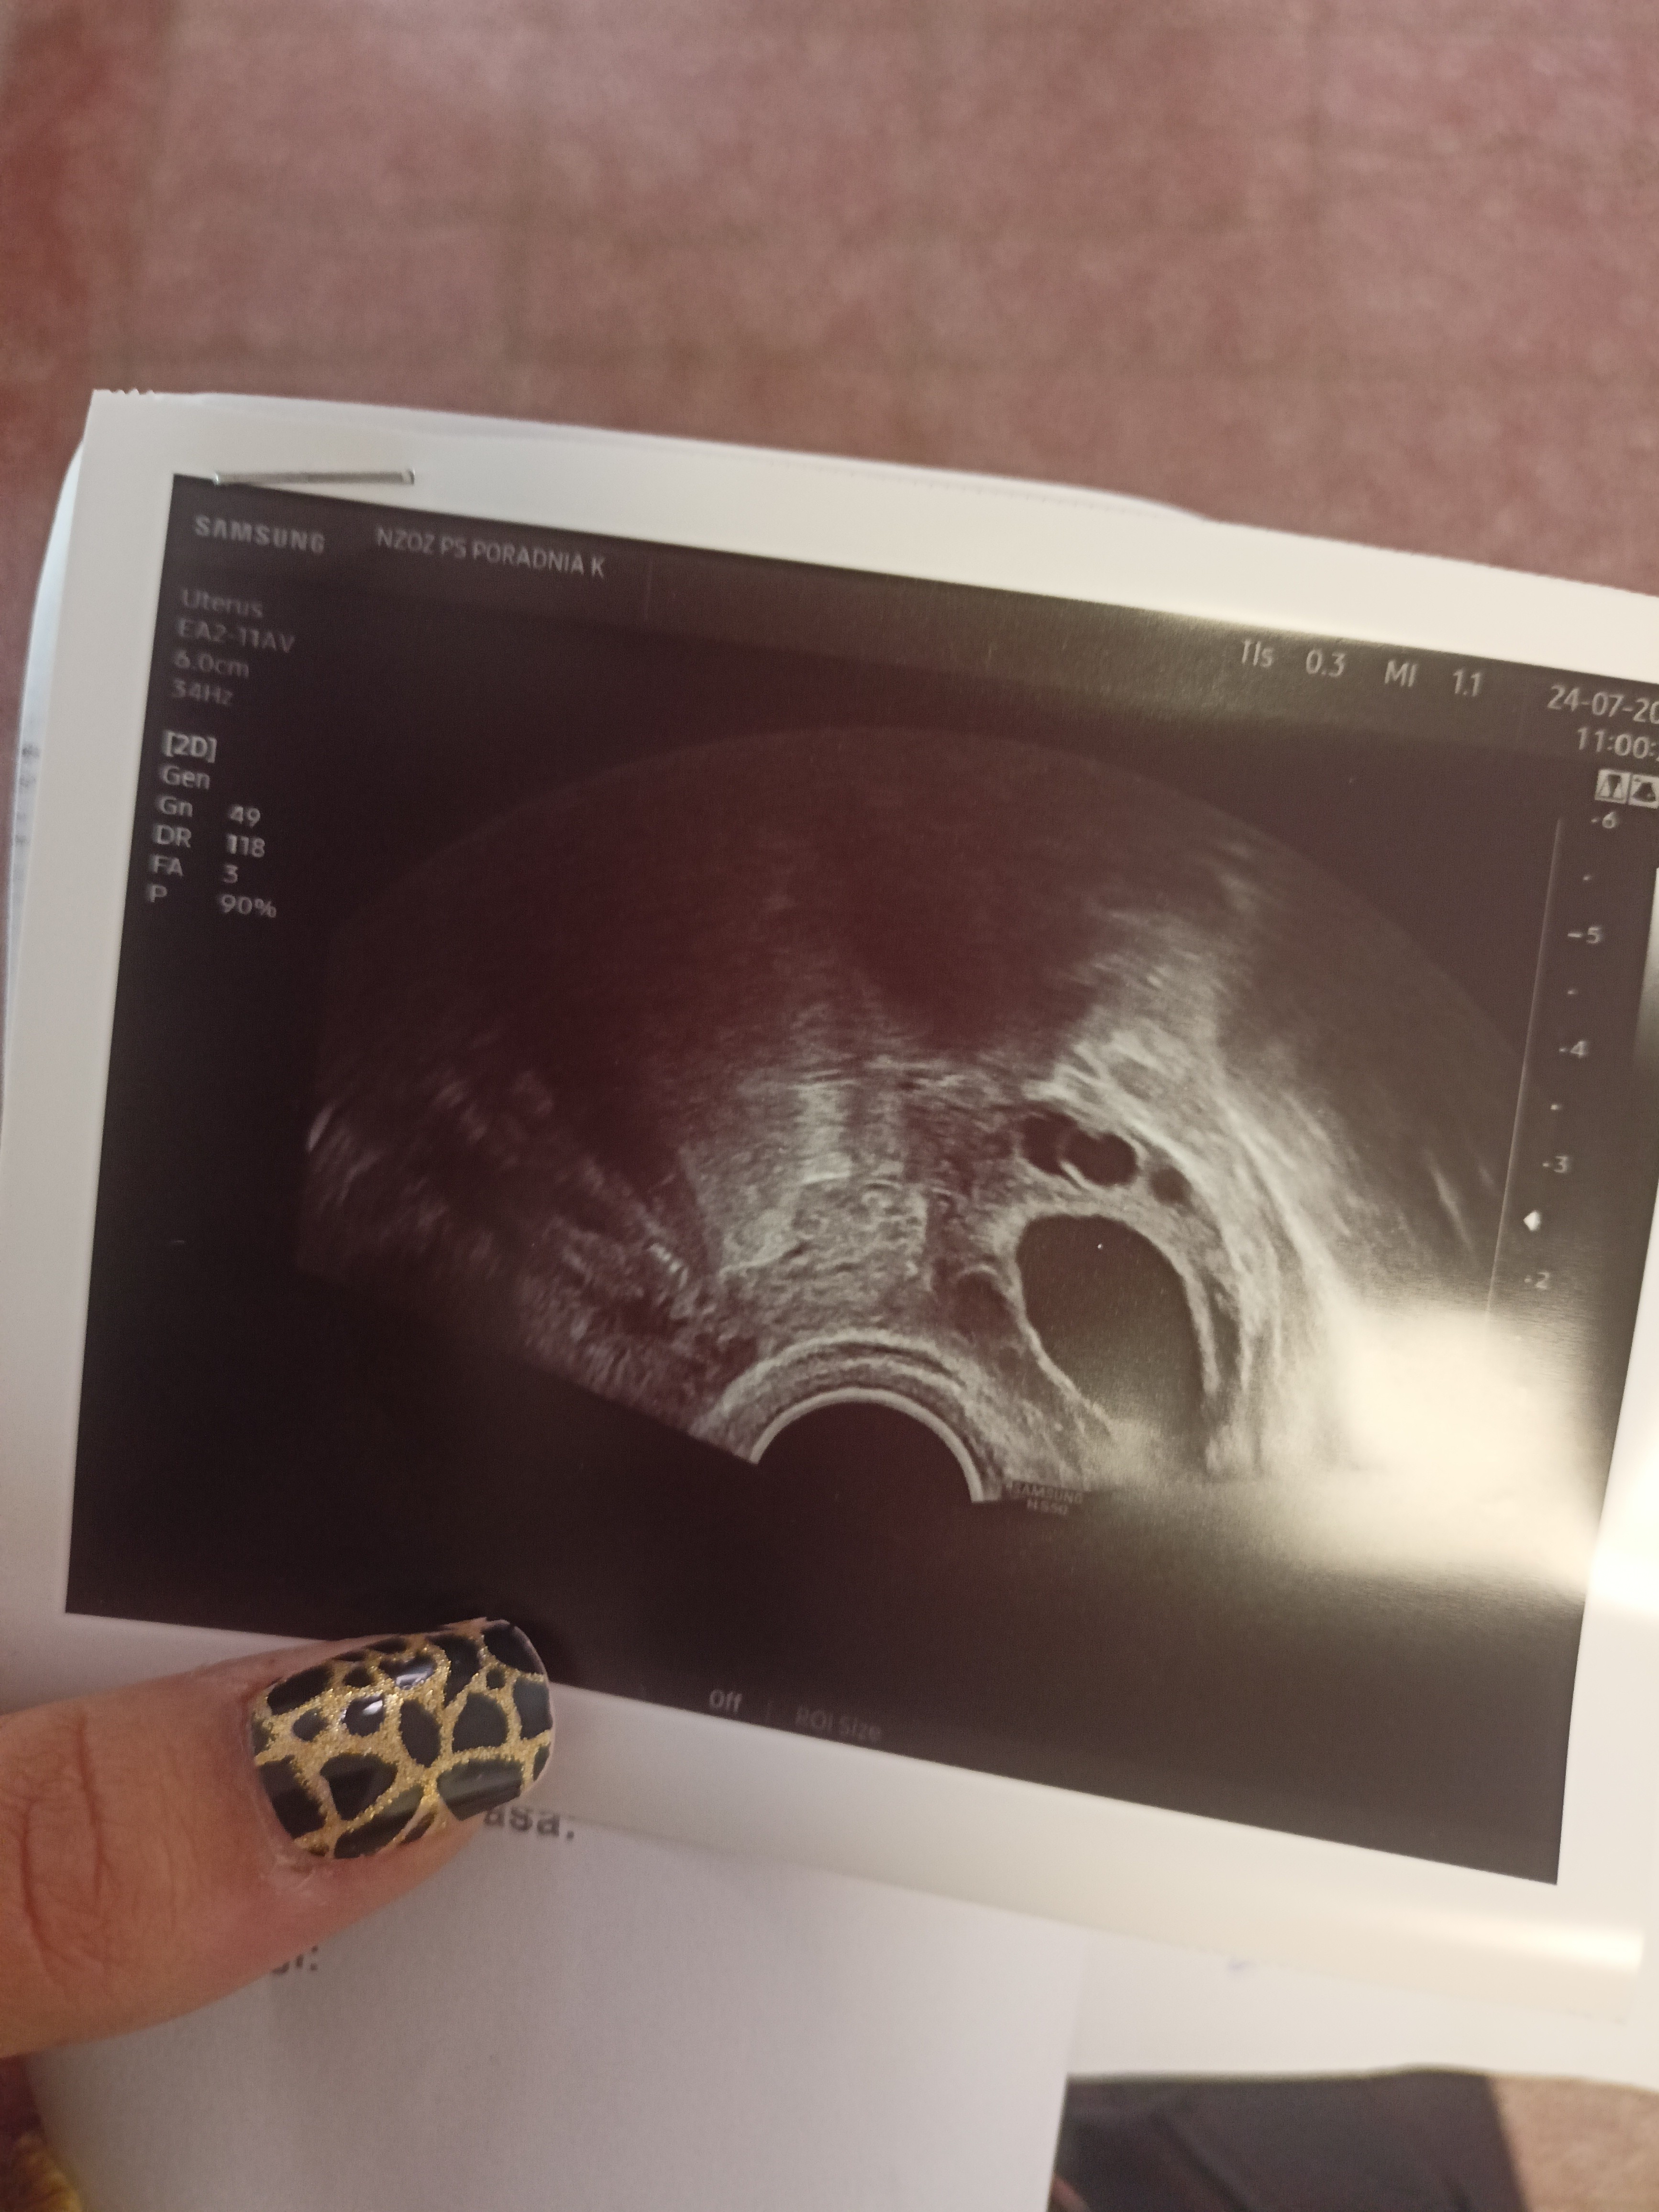

Ale nie mam żadnych torbieli ,nadżerek itp. byłam u 2 ginekologów. I żaden nie widzi nic niepokojącego. W tym cyklu postanowiłam zacząć robić testy owualcyjne do tego biorę PREGNA start . 15 DC test Lh był mega pozytywny ,tego samego dnia byłam u ginekologa powiedział ,że jest pęcherzyk z prawego jajnika 23 mm , endometrium 9 mm

stwierdził że po poprzednim cyklu który był tak rozregulowany cykl wrócił do normy. Niestety nie zapisał mnie na wizytę aby sprawdzić czy pęcherzyk pękł lecz kazał zrobić progesteron 7 dpo.